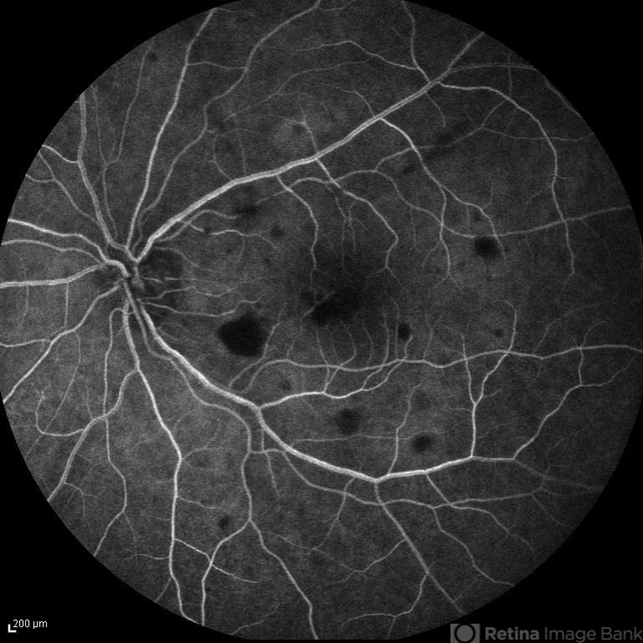

- candida endophthalmitis, endogenous endophthalmitis

- Nayereh Hadipour, Negah Eye Center, Tehran, Iran

- Fundus camera

- FA image of the left eye of a 45-year-old diabetic man with the history of urinary tract infection. The most probable diagnosis was candida endogenous endophthalmitis.